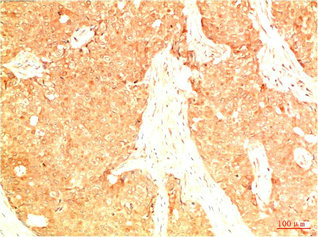

• Immunohistochemical analysis of paraffin-embedded Human Breast Carcinoma Tissue using Acetyl P53(K382) Mouse mAb diluted at 1:200.